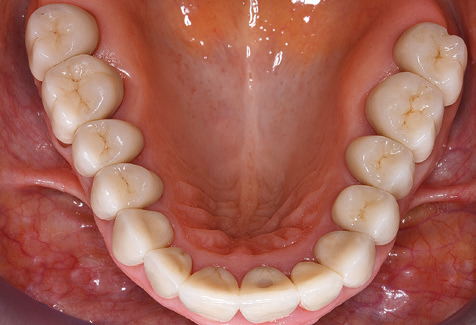

A 52-year-old patient presented in our clinic for the first time in 2004 following tooth loss in the third quadrant, expressing a desire for a new prosthetic restoration. Periodontal and radiological diagnostics revealed the need for extensive periodontological treatment. In addition, teeth 48, 28 and 27 were attributed a very poor prognosis and were subsequently extracted (Fig. 1). Following the successfully completed, systematic periodontological treatment, a fixed dental implant was inserted with the introduction of five implants in tooth regions 35, 36, 37, 46 and 47. Prosthetic treatment of the natural teeth was effected with veneered zirconium dioxide ceramic crowns; the implants were composed of two-piece, individual zirconium dioxide abutments and similarly veneered crowns made of a zirconium dioxide ceramic (Cercon base colored, Dentsply Sirona Lab). Definitive insertion of the prosthetic restoration occurred in 2005.

Due to the presence of periodontal disease, SPT was performed every three months in the first years following the insertion. The patient demonstrated a high degree of motivation and good compliance. The pocket depths recorded annually revealed a stable periodontal situation with a BOP index of below five per cent. On the basis of the stable periodontal situation and good cooperation on the patient’s part, the recall interval was extended to every six months as of the sixth year of the prosthetic function phase. Following the change in the recall interval, the respective annual documentation of the periodontal status continued to reveal a stable periodontal situation with no increase in the pocket depths and a BOP index below five per cent (Fig. 2a and b).

The ten-year check-up revealed no indications of advancing clinical attachment loss or peri-implant bone substance loss (Fig. 3).

The patient continues to visit the clinic every six months for SIT. In the following, the patient is taken as an example for demonstrating the individual working steps in a structured SPT session as it has been performed with barely any modifications over the last 12 years. Of course, some new materials and devices have been integrated into the concept over the years. This clinical case report presents the current material and device concept.